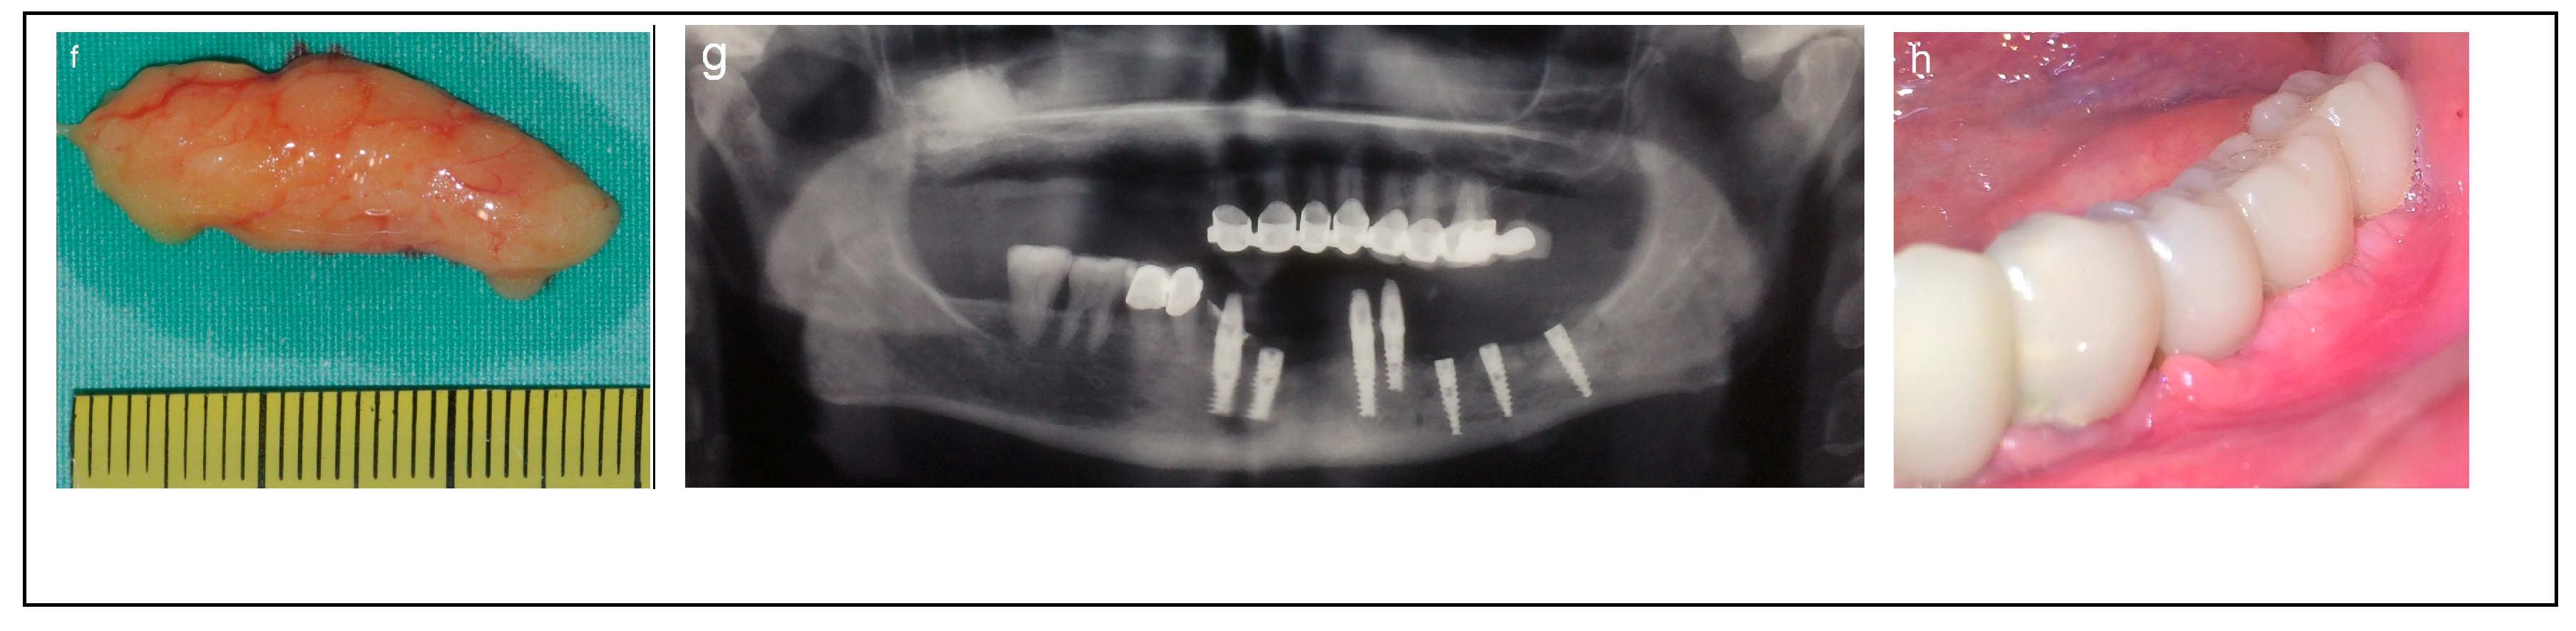

2.4. Category 4